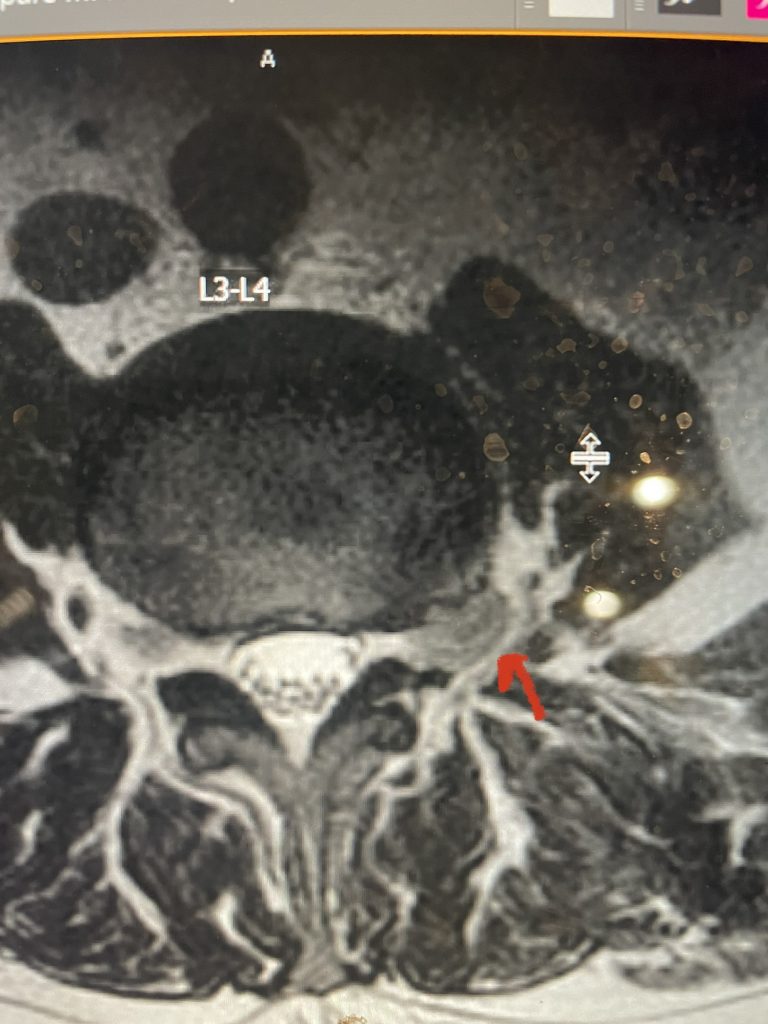

Fig 6: Axial T2-weighted lumbar MRI revealing a large extraforaminal disc herniation with severe compression of the left L3 nerve (red arrow).

Here is a case of an extraforaminal disc fragment causing severe pain and weakness: This 60-year-old male presented with severe anterior thigh pain, numbness, and weakness for 3 weeks. He had failed epidural steroid injections. His left leg buckled when he walked. Imaging revealed a massive left L3-4 extraforaminal disc herniation, beyond the facet (Fig 6). This was severely compressing the left L3 nerve root in the L3-4 foramen (Fig 7). It was felt that the patient required surgery, as he would not be able to participate in physical therapy and had a neurological deficit. We performed an extraforaminal approach and removed a massive disc fragment that was revealed as the intertransverse membrane was reflected from the L4 transverse process-facet junction. We were able to visualize the L3 spinal root exiting above that had been compressed by the large fragment we removed (Fig 8). The patient post-op had a dramatic improvement neurologically and with significantly improved pain in his leg.